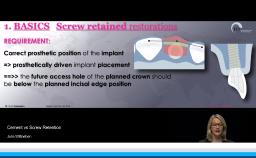

In his lecture, Dr. Gallucci addresses the critical role of interdisciplinary collaboration in implant dentistry, with a focus on the esthetic zone. He emphasizes the necessity of coordinated efforts between the surgical and restorative teams for successful outcomes in anterior zone implantation. Key topics include the precision of surgical implant placement, the importance of preserving soft tissue and contour, and the seamless transition to the prosthetic phase for effective crown loading. Dr. Gallucci also highlights the indispensability of a pre-operative restorative plan, the use of digitally guided treatment planning, and the alignment of the implant's vertical position with the planned prosthesis.

- explain the importance of collaboration between surgical and restorative teams for successful implant placement in the esthetic zone

- elaborate on the key elements of transitioning from implant placement to the prosthetic phase, ensuring a successful crown loading and esthetic integration